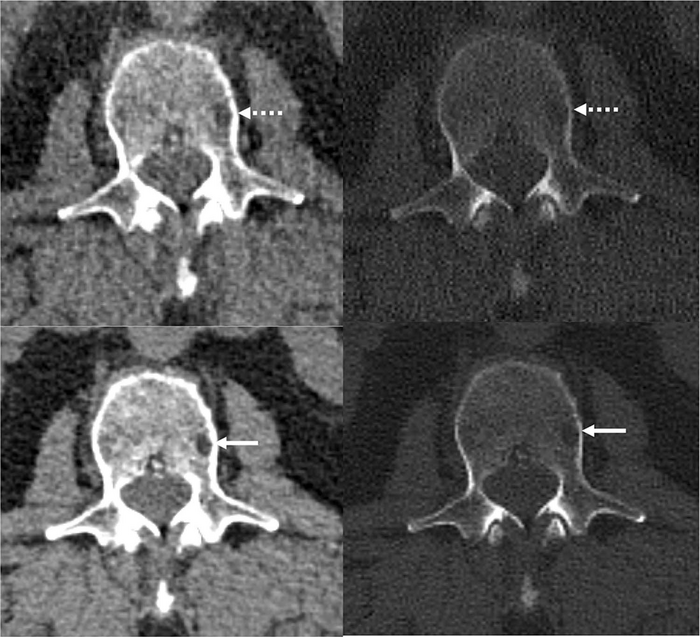

image: Reference protocol (top) and evaluated protocol (bottom) images in a 74-year-old man with multiple myeloma. The is the soft tissue reconstruction is shown, whereas the right column is the bone reconstruction. A lytic bone lesion in the L3 vertebral body is more conspicuous on the noncontrast-enhanced axial photon-counting detector CT reconstruction images (bottom; solid arrows) compared with the noncontrast-enhanced axial energy-integrating detector CT reconstruction images (top; dashed arrows). view more

The researchers also applied a deep learning AI technique developed at Mayo Clinic’s CT Clinical Innovation Center to reduce the noise in the very sharp photon-counting images. CT noise refers to an unwanted change in pixel values in the image, often loosely defined as the grainy appearance on cross-sectional imaging. The photon-counting detector CT with deep learning noise reduction demonstrated improvement in visualization and detected more lesions relative to conventional CT.

“We were excited to see that not only were we able to detect these features of multiple myeloma disease activity more clearly on the photon-counting scanner,” Dr. Baffour said, “with deep learning denoising techniques that allowed us to generate thinner image slices, we were able to detect more lesions than on the standard CT.”